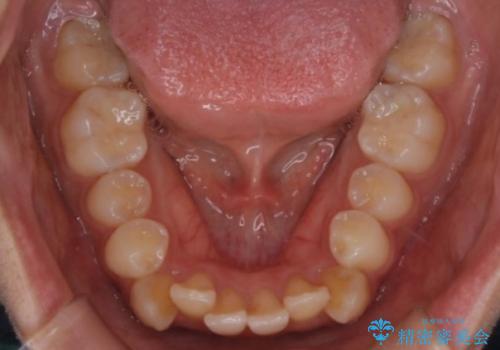

- 八重歯を主訴に来院されました。4番の歯を4本抜歯し、八重歯を並べる計画をたてました。

抜歯をし、スペースを確保したことにより八重歯をきれいに並べることが出来ました。